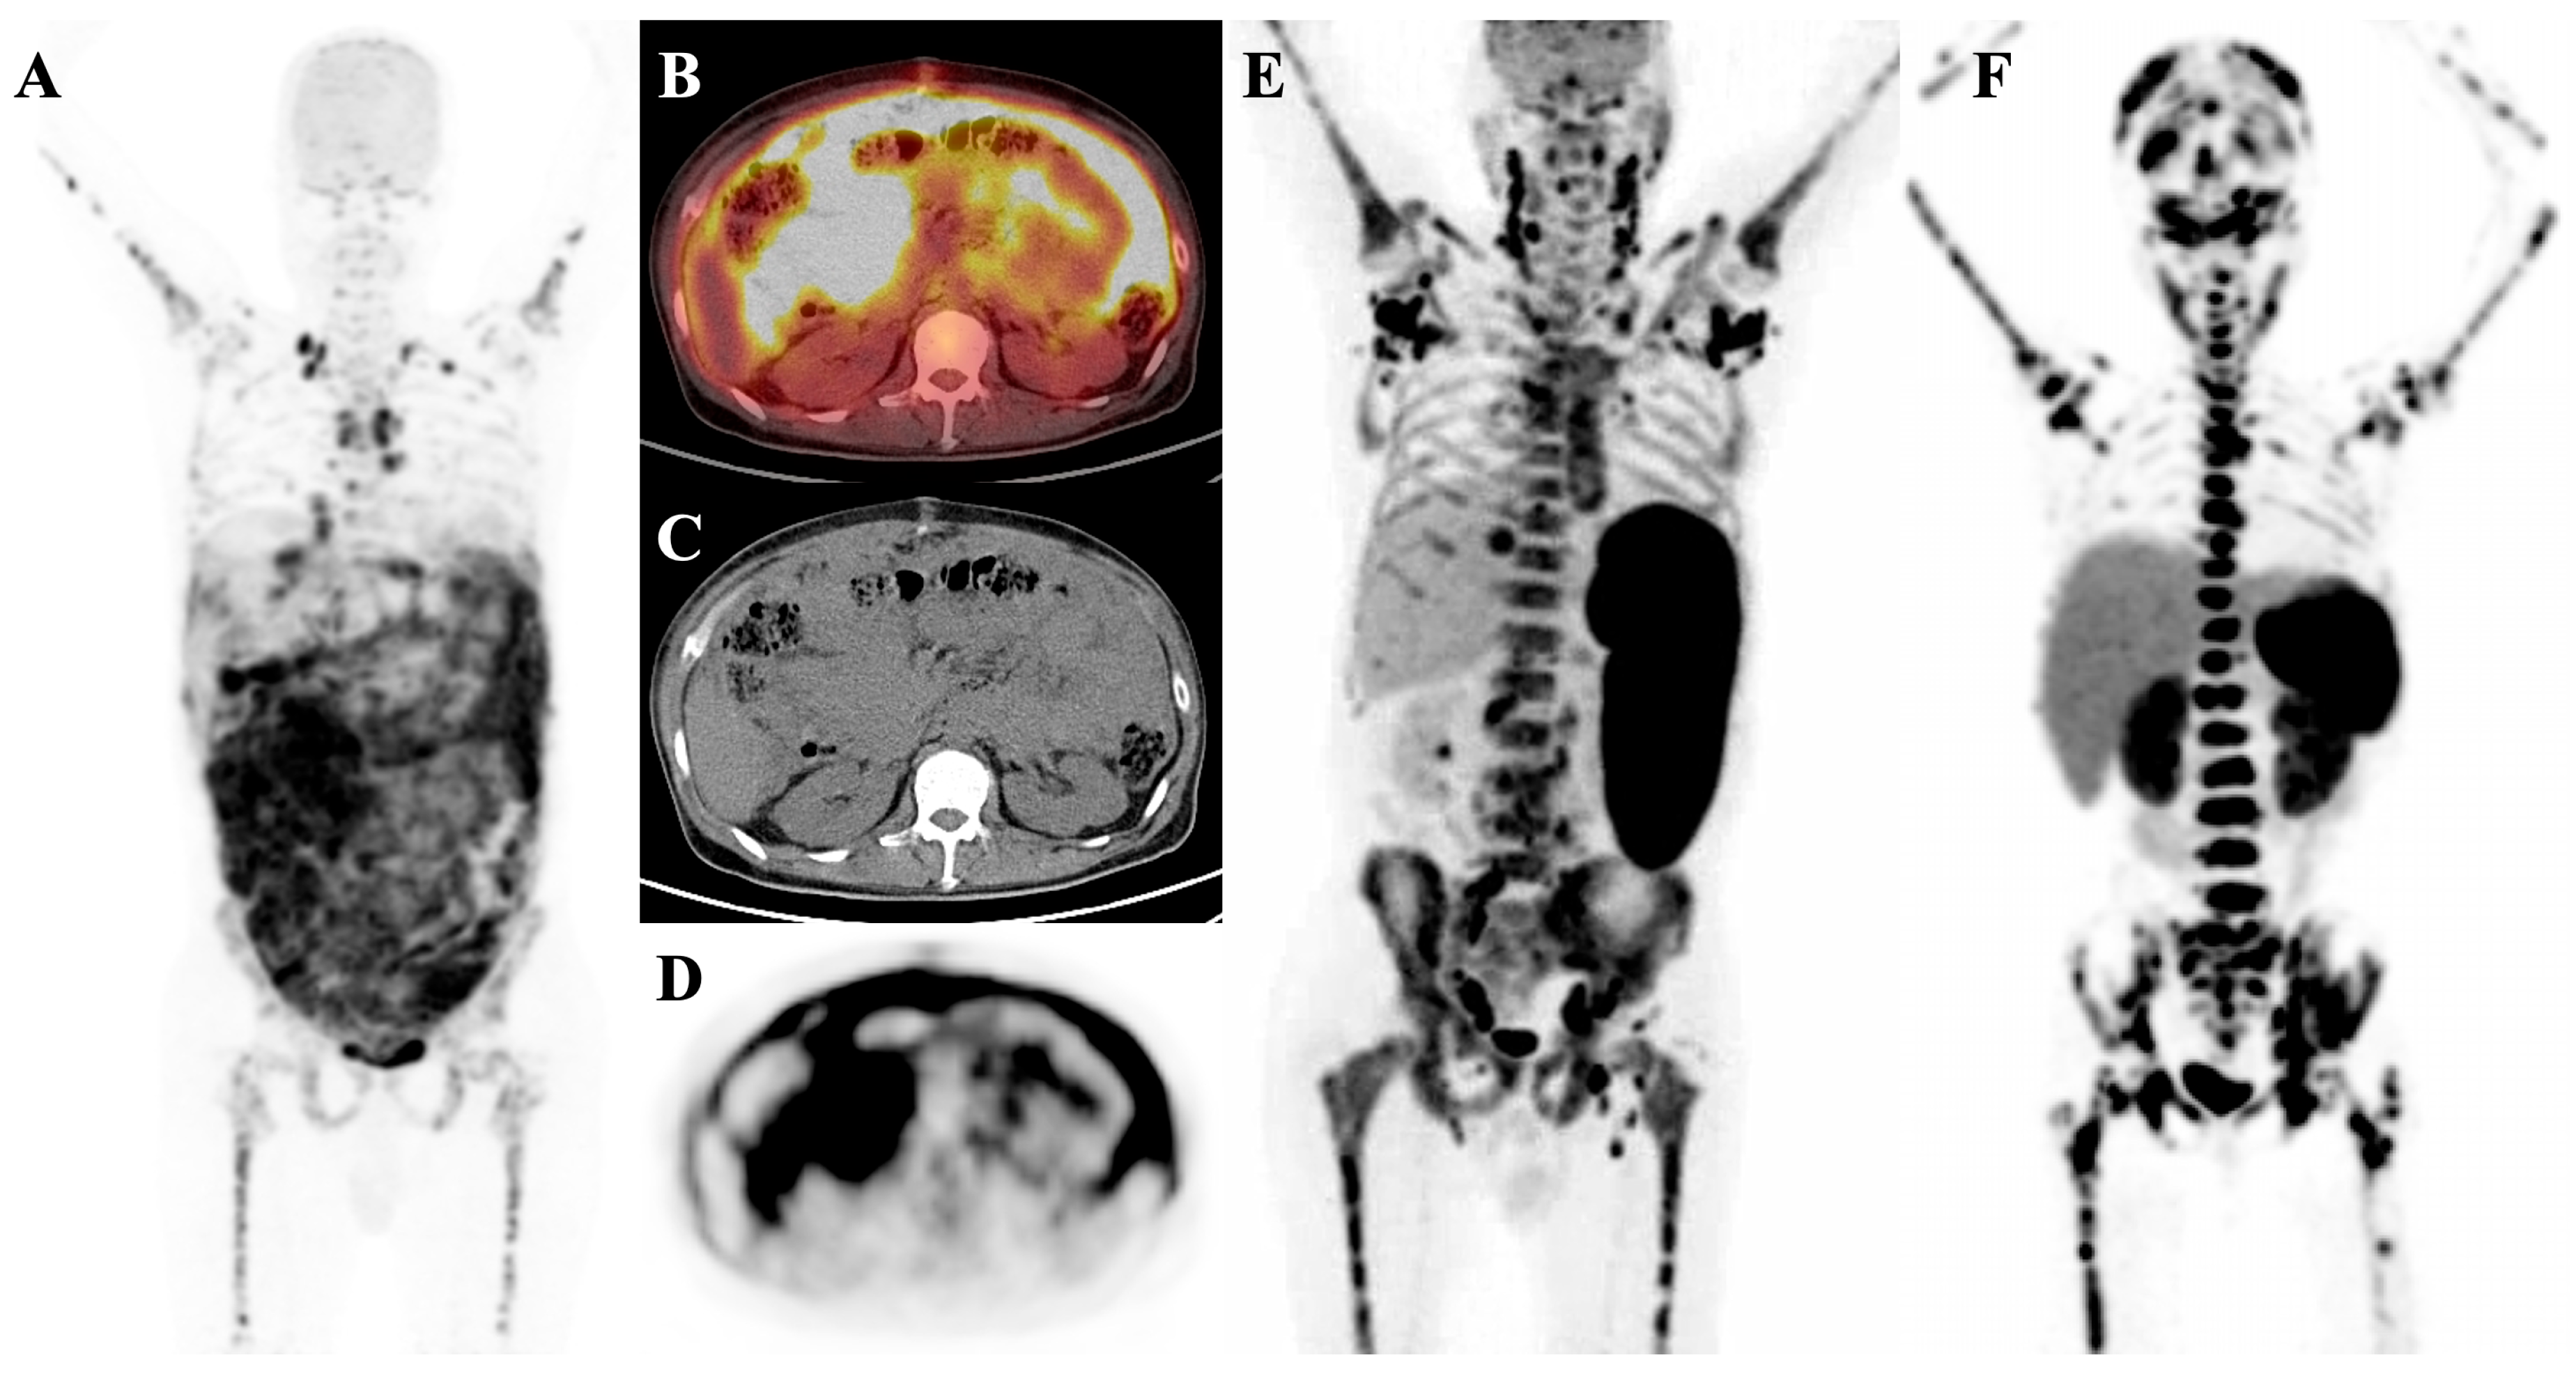

7.2. Metabolic Superscan

7.3. Distinguishing Metabolic Superscan from Metastatic Superscan